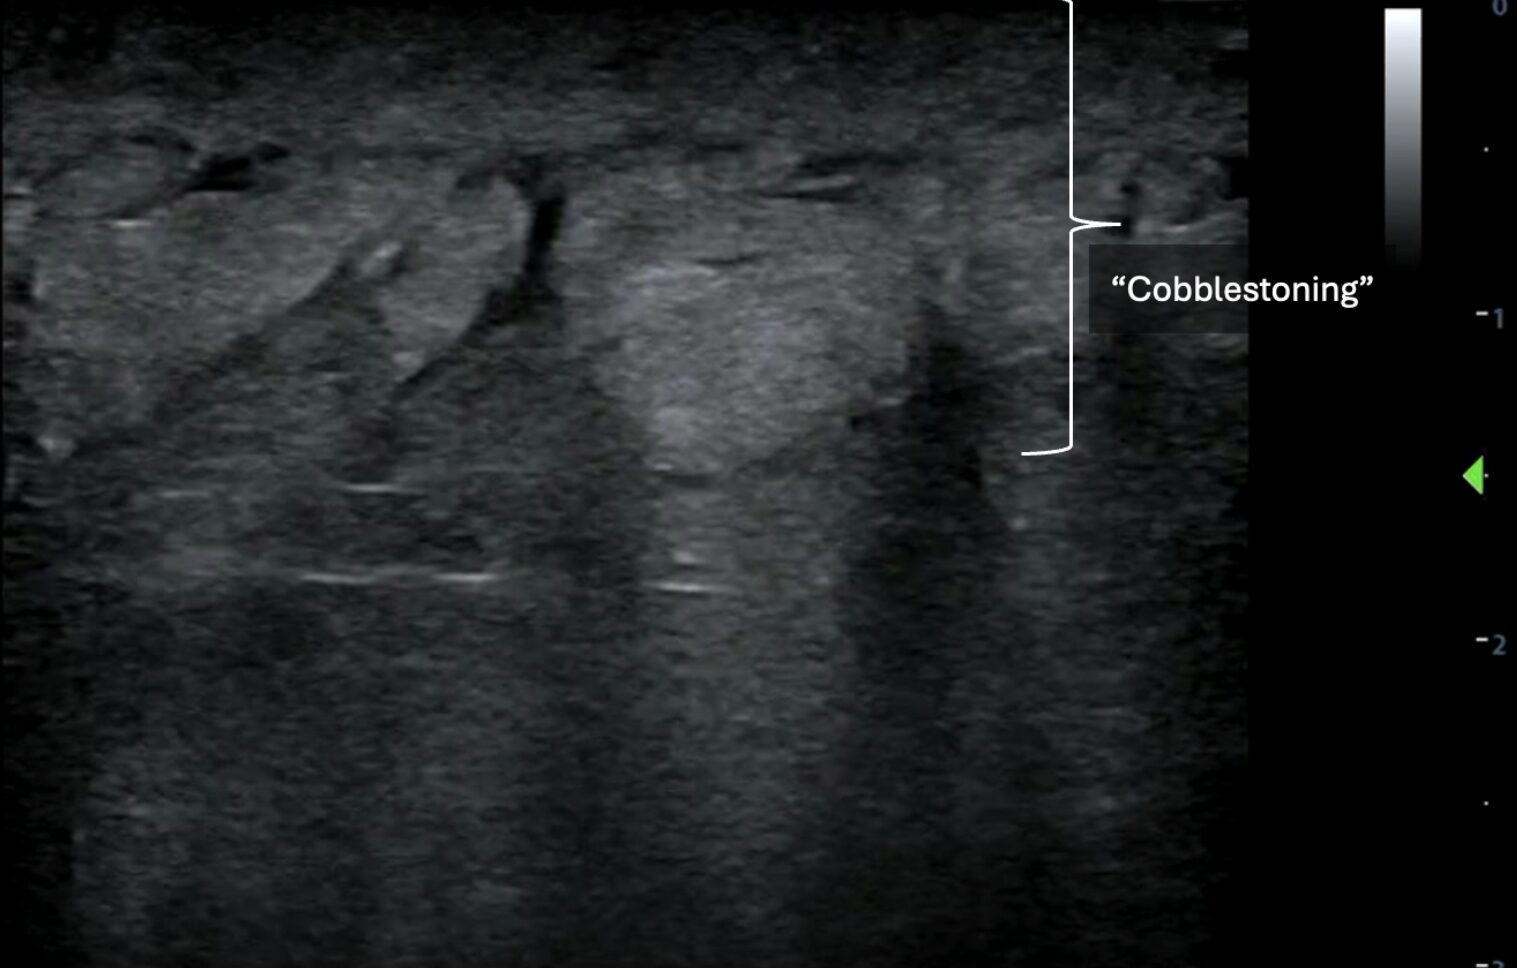

As necrotizing soft tissue infections are part of a continuum of skin and soft tissue infections that includes cellulitis and abscesses, it is important to recognize and distinguish these diagnoses using POCUS. Cellulitis demonstrates a cobblestone appearance on POCUS but lacks other findings characteristic of NSTI, such as subcutaneous emphysema and fascial fluid (Image 6, Video 5).

Image 6: Disorganized, globular changes localized to the subcutaneous tissue known as “cobblestoning.” Images courtesy of Dr. Shepherd and Dr. Alerhand.

Video 5: Video clip of the above still image demonstrating “cobblestoning.” Images courtesy of Dr. Shepherd and Dr. Alerhand